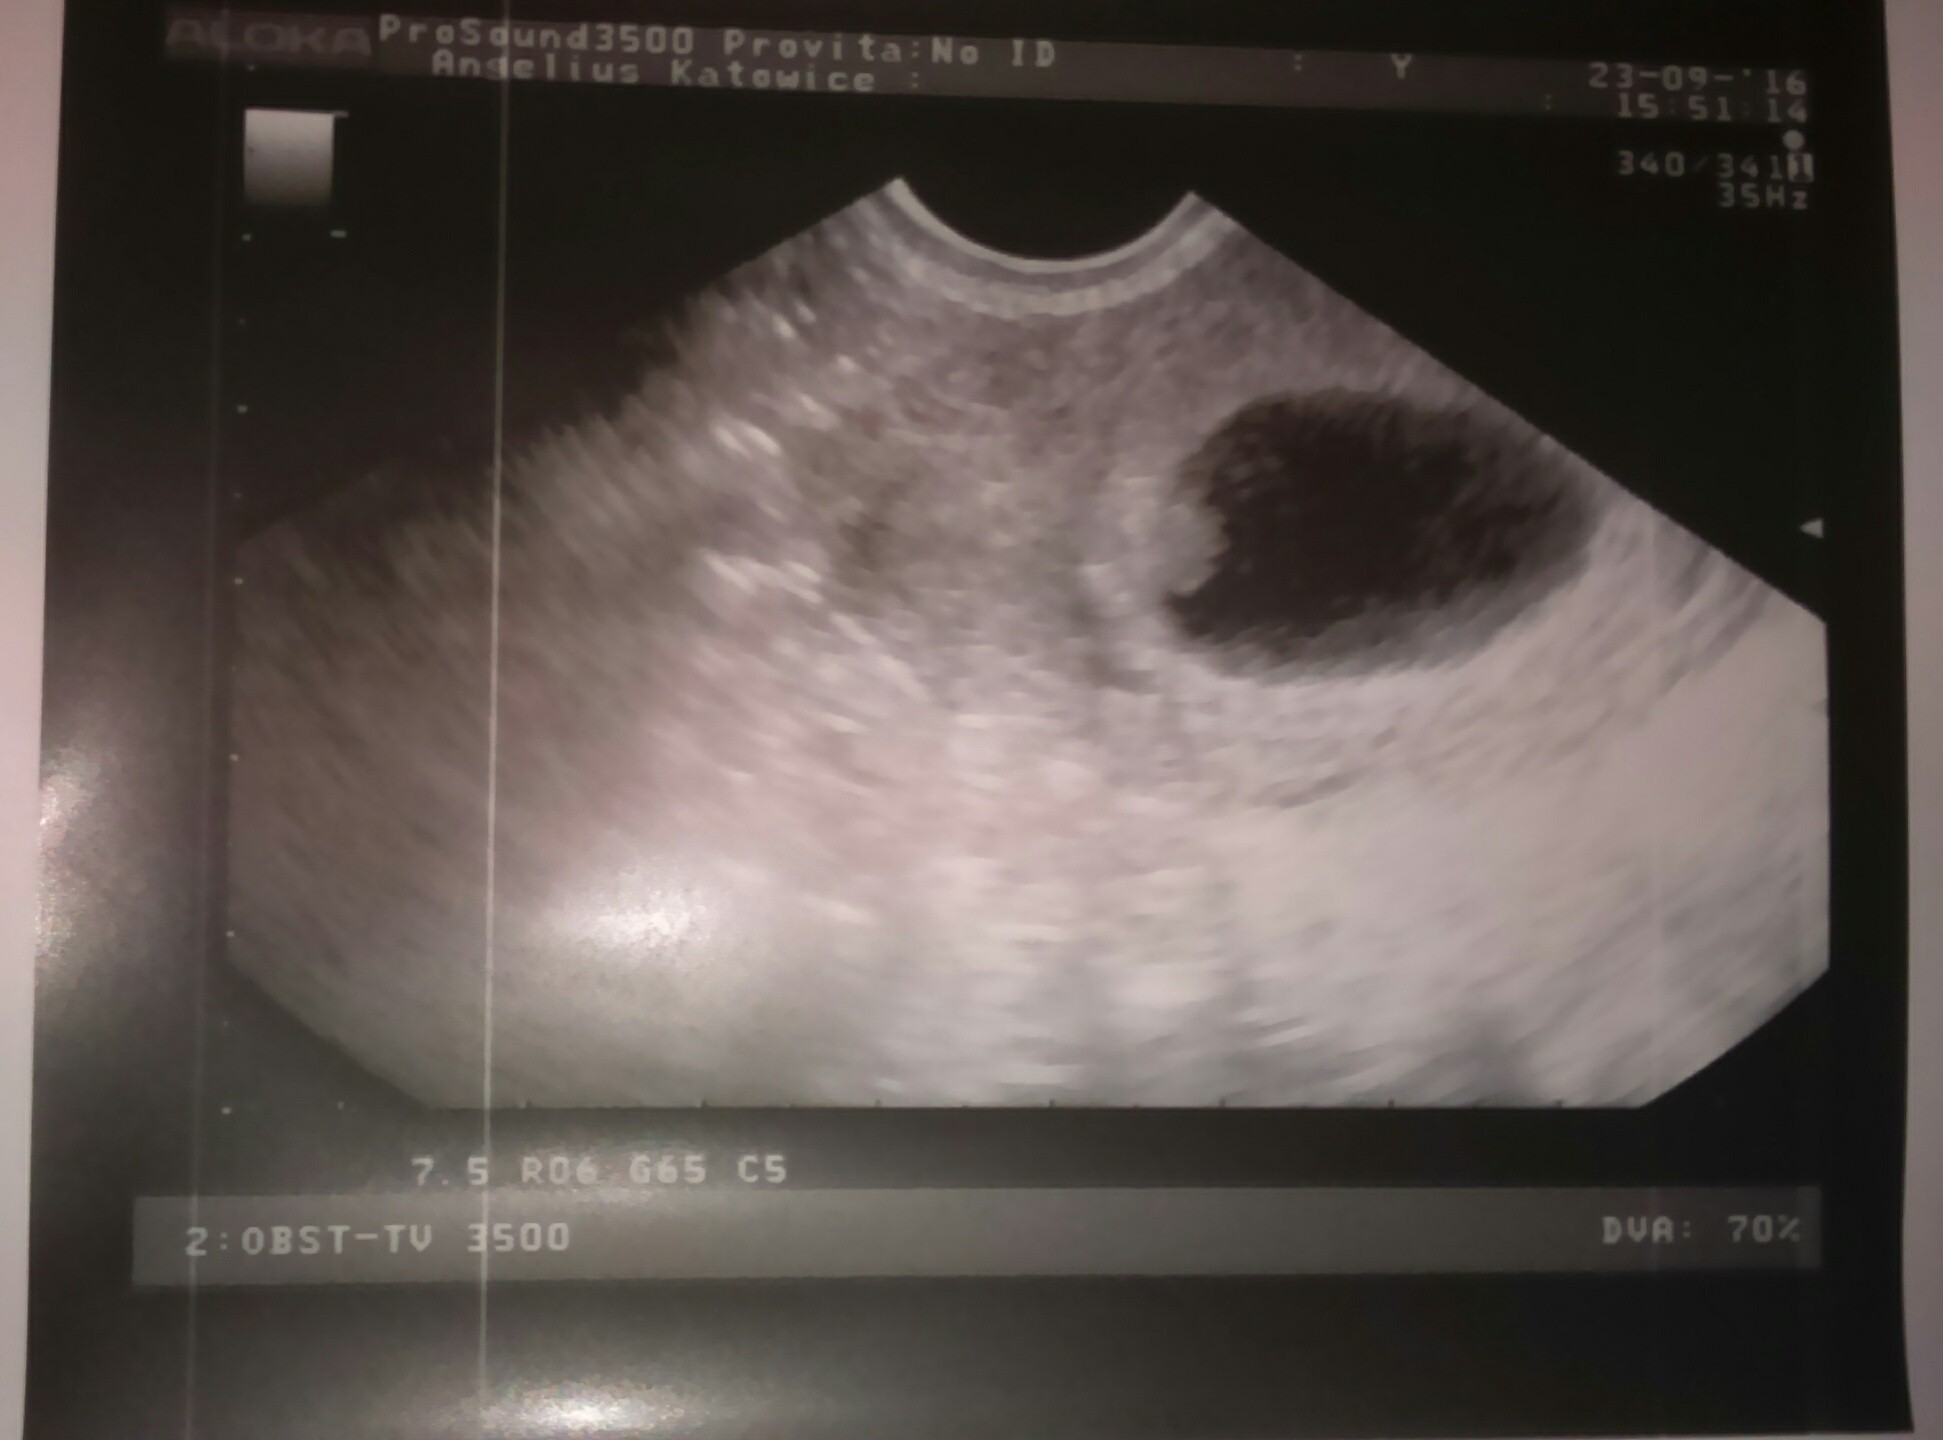

Kochane, to był najpiękniejszy widok na świecie :) Warto było przez to wszystko przejść. Mam już kartę ciąży, Dzidzia jest jedna i ma piękne serduszko, widziałam jak bije :)

A oto i moje maleństwo :)

Załączniki

• IMG_20160923_184743.JPG

IMG_20160923_184743.JPG

234,8 KB · Wyświetleń: 142